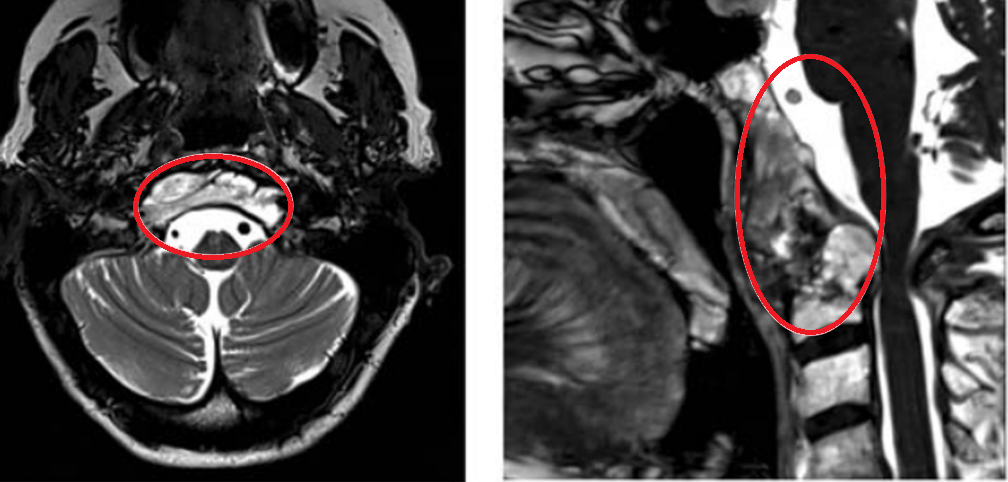

▼图a-b术前MR显示颅颈交界区巨大脊索瘤,51.3×74.3×25.9 mm大小,浸润性生长。

▼图显示脊索瘤向周边浸润生长,下至C5-C6水平的脊髓瘤侵犯浸润。

▼F术后MRI显示肿瘤完全除